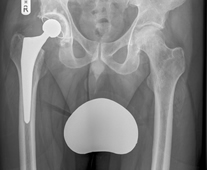

X-ray showing a Right Total Hip Replacement. Here the components are a cemented highly cross-linked polyethylene cup (Reflection™), a cemented femoral stem (Exeter™), with a ceramic head. Enlarge